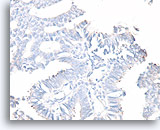

Papillair carcinoom, Borst FNA, Celblok.

De afwezigheid van een immunokleuring met calponine duidt op een diagnose van een papillair carcinoom.

40X

Papillair carcinoom, Borst FNA, Celblok.

De afwezigheid van een immunokleuring met calponine duidt op een diagnose van een papillair carcinoom.

40X

Papillair carcinoom, Borst FNA, Celblok.

De afwezigheid van kleuring met p63 helpt een papilloom uit te sluiten.

40X

Papillair carcinoom, Borst FNA, Celblok.

De afwezigheid van kleuring met p63 helpt een papilloom uit te sluiten.

40X